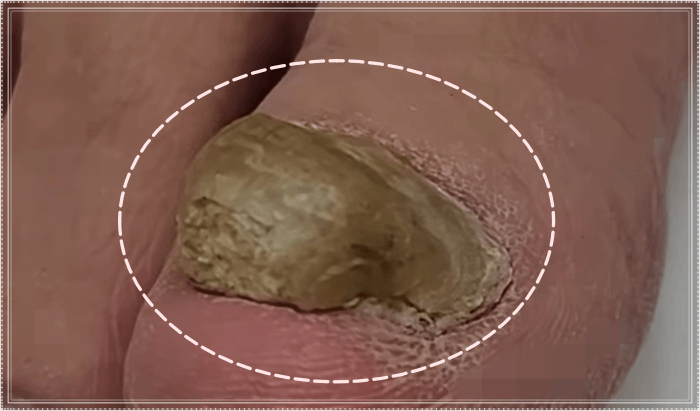

발톱에 무좀균이 침투하면 발톱의 단백질을 갉아먹으며 그 안을 변형시킵니다.

발톱 무좀 증상은 발톱이 점점 두꺼워지면서 노란색이나 갈색으로 변색되기도 하고, 심하면 하얀 가루가 생기며 부스러지기도 합니다.